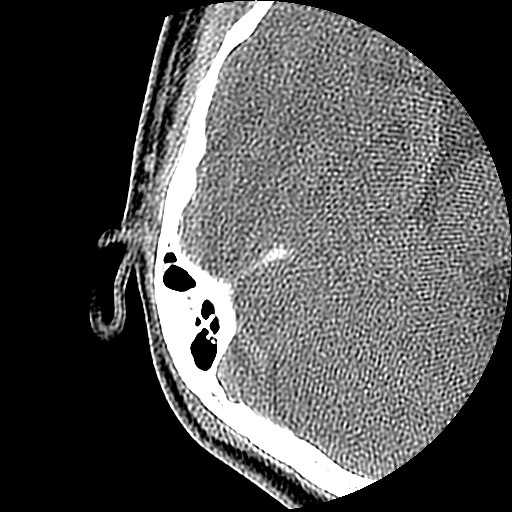

以下是引用随光逐影在2009-8-19 7:25:00的发言:[br]右侧慢性中耳乳突炎,右侧中耳腔及外耳道肉芽肿或胆脂瘤形成。